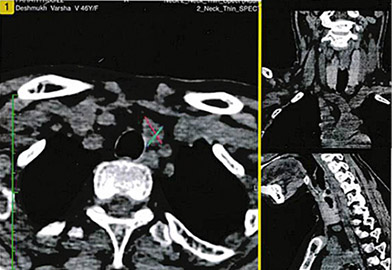

She was further evaluated with Sestamibi scan which confirmed a left inferior parathyroid adenoma of size 15x12x8 mm, abutting the inferior pole of left lobe of thyroid gland (Figure 2). Bone marrow biopsy from iliac crest lesion was suggestive of brown tumor of hyperparathyroidism as well. Dual energy X-ray absorptiometry (DEXA) or bone density scan was done to assess the severity and was suggestive of severe osteopenia at spine (Z score ‒4.9) and femur neck (Z score ‒4.5).

A. Axial uptake image |

B. Transverse view – parathyroid marked with green-red cross |

Figure 2. Sestamibi scan showing left inferior parathyroid adenoma |